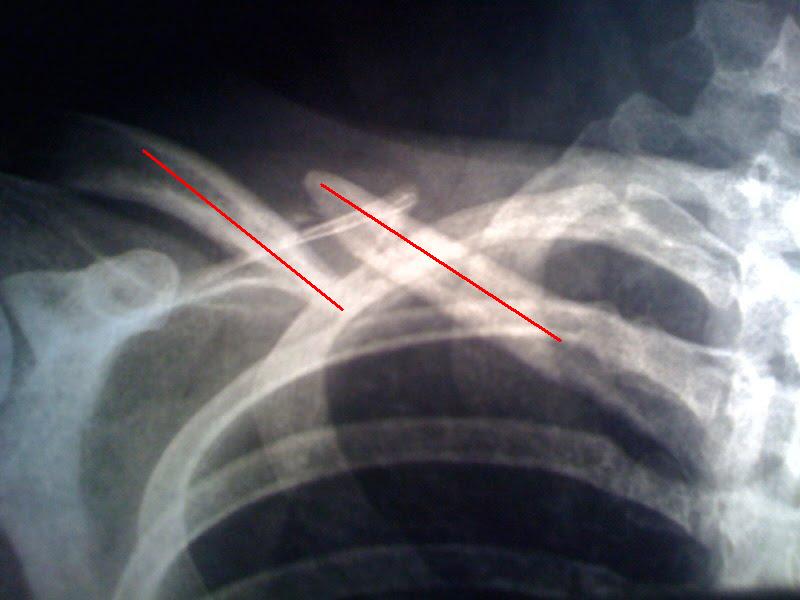

Vergleich nach 4 Monaten

Links das Bild vom 02.08.2009, frisch nach dem Unfall. Rechts das von gestern. Ich hatte nochmal einen Termin bei einem weiteren Arzt. Jetzt habe ich eine Überweisung zum Uniklinikum in der Tasche und noch ein weiterer Arzt darf über das Schlüsselbein philosophieren. Ich denke dann fällt auch die Entscheidung ob noch operiert wird oder nicht…